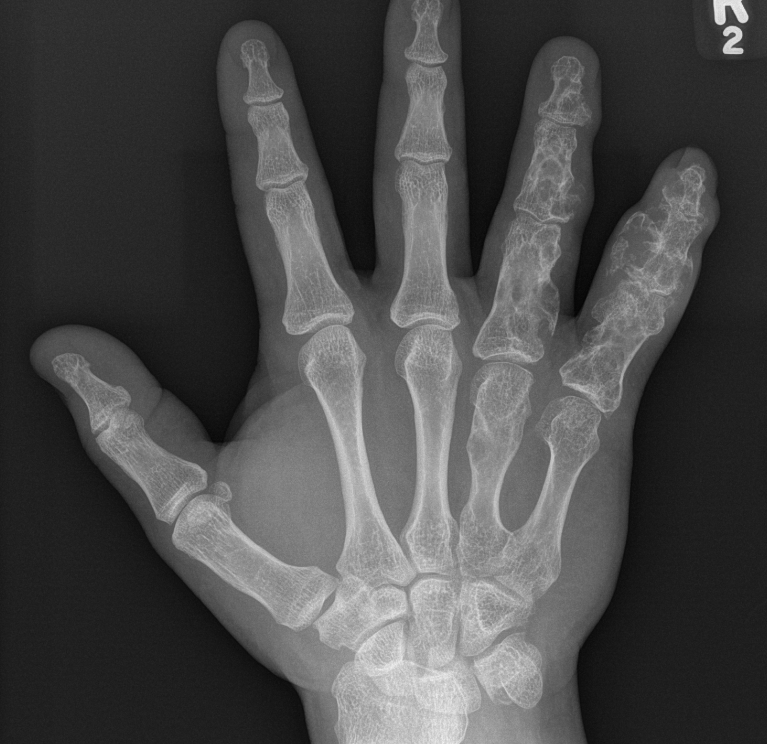

Hands > feet

Hand & Feet

Often present in first decade of life with palpable masses on hands and feet

- cosmetic issues / stiffness / pathological fractures

Klein et al J Hand Surg Am 2018

- 10 pediatric patients with metacarpal or phalangeal enchondromas

- curettage and corticoplasty (trimming of excess bone) for hand enchondromas

- improved range of motion and cosmesis